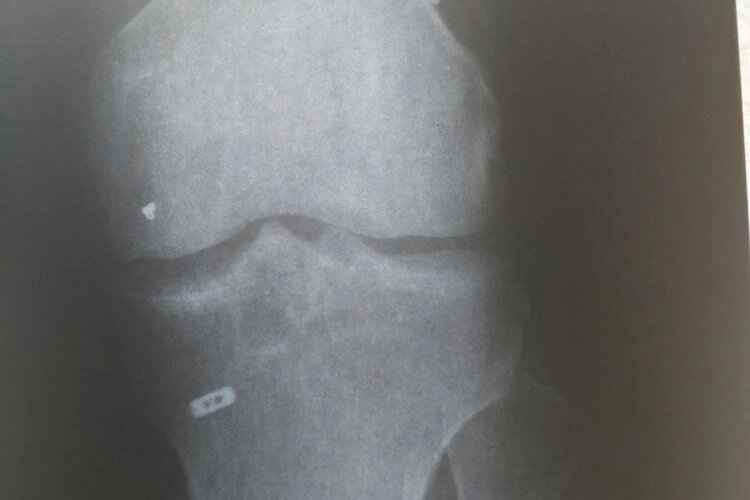

Спустя десять месяцев после операции Ерлан обратился к казахстанскому хирургу. Результаты МРТ оказались шокирующими: в заключении указывалось на присутствие инородного тела в колене, а также на то, что связка не функционирует должным образом. Чтобы подтвердить диагноз, мужчина сделал рентген — снимок не оставил сомнений: в суставе отчётливо просматривался металлический фрагмент с чёткими контурами, формой и размерами.

Врачи пояснили, что обнаруженный предмет — часть хирургического инструмента, оставленного во время операции. Кроме того, стало ясно, что связка так и не восстановилась.